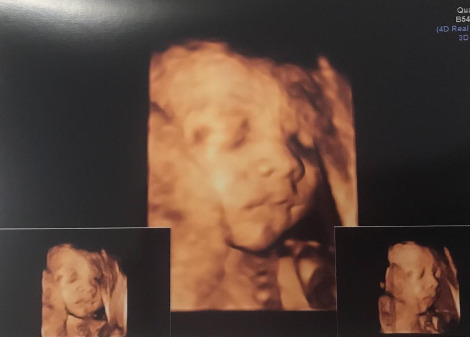

11월 마지막 주, 둘째 아이가 태어난다. 원래 예정일은 12월 초이지만 수술을 할 생각이라 출산일을 조금 당겨 잡은 것이다.

3.68kg의 우량아로 우리 앞에 나타난 첫째